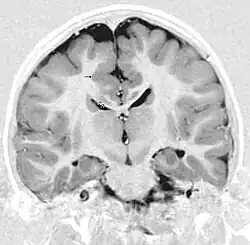

Gray matter heterotopia

Gray matter heterotopia is a neurological disorder caused by gray matter being located in an atypical location in the brain.[1]

Periventricular means beside the ventricle, while subependymal (also spelled subepydymal) means beneath the ependyma; because the ependyma is the thin epithelial sheet lining the ventricles of the brain, these two terms are used to define heterotopia occurring directly next to a ventricle. This is by far the most common location for heterotopia. Patients with isolated subependymal heterotopia usually present with a seizure disorder in the second decade of life.

Subependymal heterotopia present in a wide array of variations. They can be a small single node or a large number of nodes, can exist on either or both sides of the brain at any point along the higher ventricle margins, can be small or large, single or multiple, and can form a small node or a large wavy or curved mass.